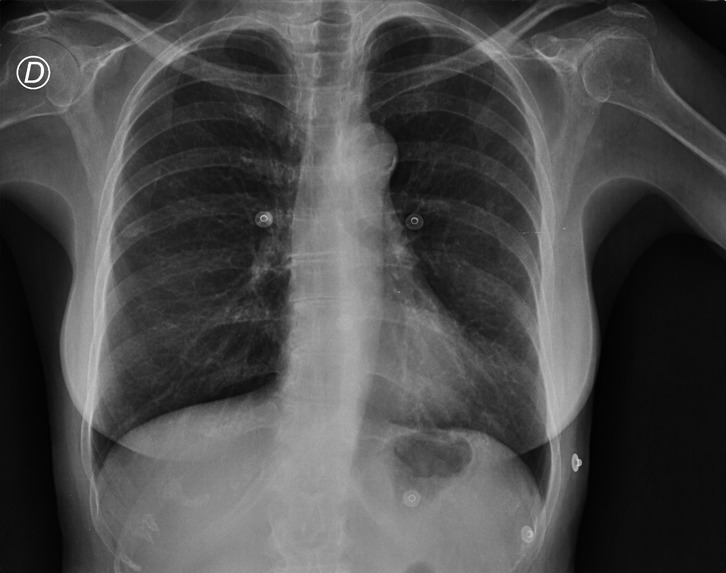

The pandemic has changed our lifestyle and until today it is affecting us, and it is necessary to know every information to keep us and our loved ones safe. With the virus mutating and increased cases of asymptomatic cases now COVID can be being detected using the chest x-rays as it affects the respiratory system first. According to LSU radiologists, these chest x-rays can be used for rapid diagnosis where there are limited testing and delayed results. And as we all know prevention is better than cure with a lot of advice from everyone there is a lot of confusion over the right and spam news. There is a need for expert advice, current news, and rapid diagnosis.

Virtual communication is the new future. In order to help the nurses, patients, and doctors in an effective way, we have created an application that predicts whether a person has COVID or not using Xray inputs from the user and giving advice on the results, The application also gives all the latest information on COVID-19, the preventions following the CDC guidelines, the statistics of COVID-19 cases, and an easy platform to contact doctors to seek advice virtually.